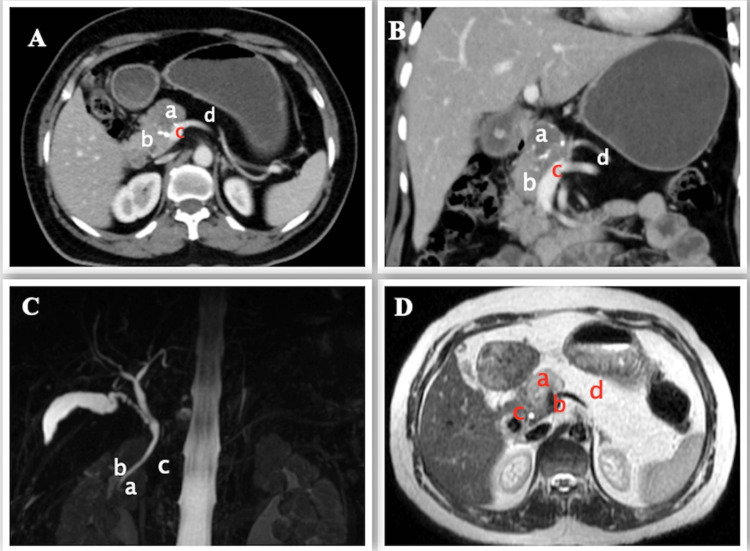

Following this, a triphasic contrast-enhanced computed tomography (CECT) scan showed a tumor arising from the head of pancreas with 180-degree abutment of the anterior wall of the portal vein with loss of fat planes (Figure 1A, 1B). The tumor was adherent to the common hepatic artery and gastroduodenal artery with no metastasis. However, the body and tail of the pancreas could not be visualized anterior to portal confluence and splenic vein (Figure 1A).

Figure 1. Preoperative imaging.

A, B - CECT (axial and coronal view) scan showing SPEN (a) arising from the head of pancreas (b) with infiltration of the portal vein (c) and agenesis of dorsal pancreas (d)

C - MRCP showing normal ventral pancreatic duct (of Wirsung) (a), the common bile duct (b), and absence of dorsal pancreatic duct (c)

D - MRI showing tumor (a) just above the portal confluence (b), close by distal CBD (c) and distal pancreas replaced by fat (d)

CECT: contrast-enhanced computed tomography, SPEN: solid pseudopapillary epithelial neoplasm, MRCP: magnetic resonance cholangio-pancreatography, CBD: common bile duct

On MRCP, the dorsal pancreatic duct (of Santorini) and the minor duodenal papilla could not be visualized. However, the ventral pancreatic duct (of Wirsung) and the common bile duct (CBD) were normal (Figure 1C). The distal CBD was close to the tumor (Figure 1D), with evidence of loss of fat planes with the portal vein but no evidence of loss of flow void.